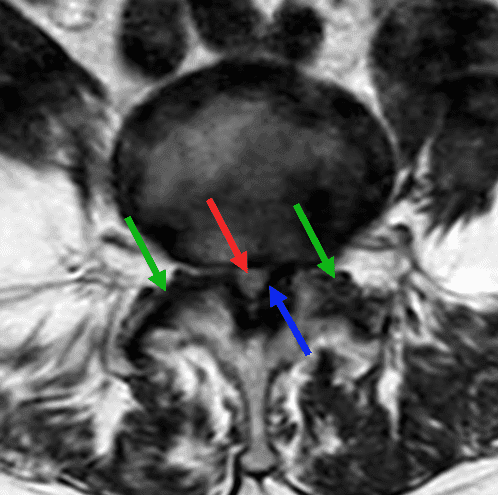

Présentation classique d'un canal lombaire rétréci (flèche rouge) en L4-L5, d'origine mixte : étalement discal, zygarthrose bilatérale (flèches vertes) avec épaississement des ligaments jaunes (flèche bleue), et antélisthésis de grade I de L4 (flèche jaune).

L'étude dans le plan axial en pondération T2 permet de mettre en évidence la disparité de calibre du canal lombaire en amont et en aval du rétrécissement canalaire. Il s'agit ici d'un rétrécissement canalaire de grade D de la classification de Lausanne.

Axial T2